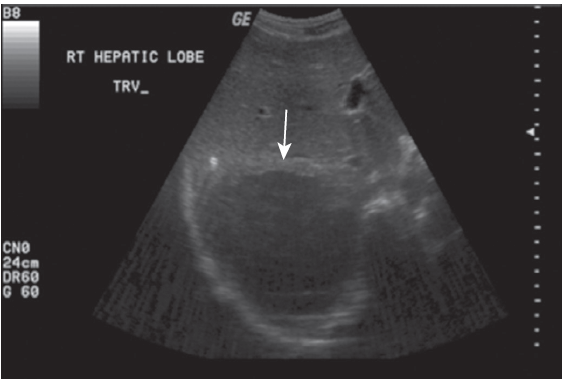

- 초음파

- 화농성 - 불규칙한 경계를 보인다.

- 아메바성 - 둥글고 뚜렷한 경계를 보인다.